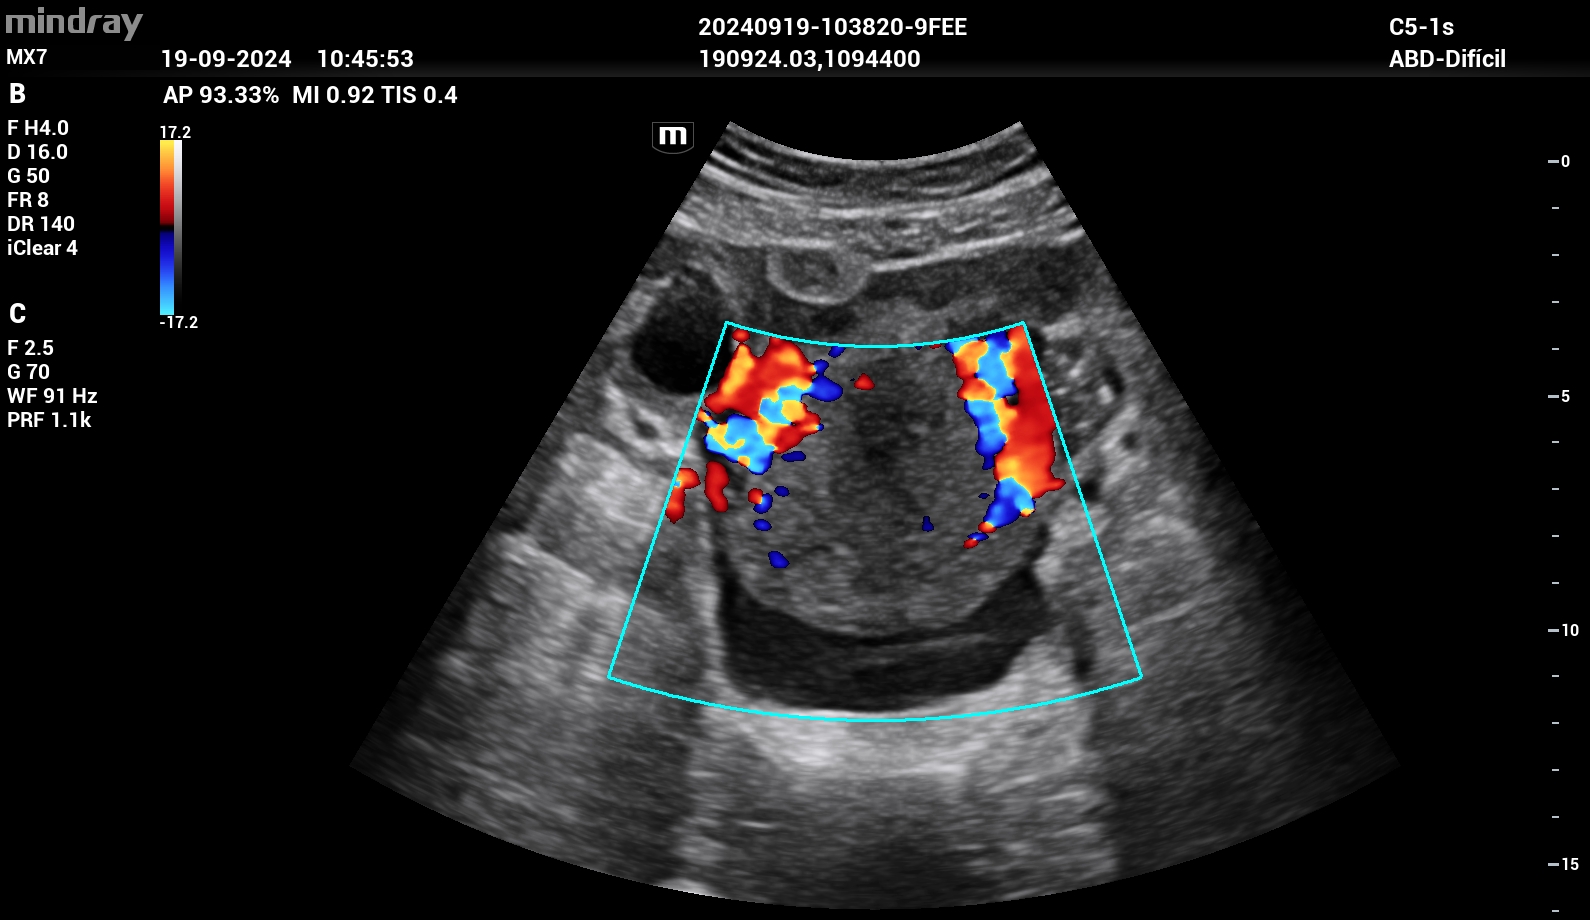

Se realizó ecografía clínica donde se objetivó líquido libre intraabdominal en espacio de Douglas. Útero en anteversión sin vesícula gestacional en interior. En región paraovárica derecha presentaba imagen ecomixta de 40 x 31 mm sugestiva de embarazo ectópico.